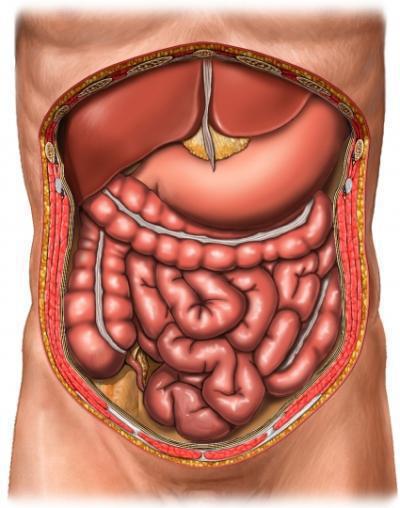

hasüregben

A fő tartály MINTAVÉTELRE, tárolására élelmiszer gyomorban. Nem található a rekeszizom alatt, a bal oldalon, a hashártya. A hátsó, csak alul a gyomor a hasnyálmirigyben. Ez lebontja zsírok, szénhidrátok, fehérjék és gyárt glukagon és inzulin - a legfontosabb hormonok.

A jobb oldalon, a rekeszizom alatt, a máj található. Összehangolt munka az emberi test függ a szervezetben. Máj - a fő szűrő. Az alsó része a máj, a mélyedés található epehólyag, amely fontos szerepet játszik az élelmiszer-feldolgozás. A bal oldalon a hipochondria a lép, védi a szervezetet a különböző fertőzések, valamint a vérveszteségtől.

Gyomor alsó hashártya helyet foglalja el a vékonybélben, amely egy hosszú bonyolult csőben. Az elején a vastagbél (vakbél) - a jobb oldalon. Ezután vastagbél hashártya folyik a tetején, és leesik a bal oldalon. Vakbél lásd Melléklet. Colon átjut egy egyenes vonal, véget ér a végbélnyílás - aljzatba, amelyen keresztül eltávolítjuk a széklet tömegét.